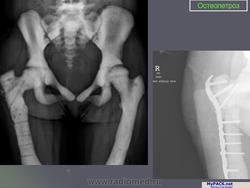

Морфологические изменения при остеопетрозе объясняются недостаточной активностью остеокластов. Макроскопически видно, что кости теряют костномозговой канал, концы длинных костей приобретают грушевидную форму (колбовидная деформация). Невральные отверстия становятся маленькими и сдавливают выходящие нервы. Первичная спонгиоза, которая удаляется в ходе начального роста, остается и заполняет полость костномозгового канала. Она не оставляет места для кроветворной части костного мозга и препятствует формированию зрелых костных балок. Формирующаяся кость не восстанавливает естественные структуры и имеет тенденцию к сохранению в грубоволокнистом состоянии. В конечном итоге эти внутренние аномалии делают кость хрупкой. Гистологически существенных изменений в количестве остеокластов обнаружить не удается, их число может быть чуть увеличенным, нормальным или уменьшенным.

Лабораторная и инструментальная диагностика. Характерны гипокальциемия, гипофосфатемия и повышение уровня ПТГ в сыворотке (вторичный гиперпаратиреоз). Всасывание кальция в кишечнике усилено, но гипокальциемия тем не менее сохраняется, поскольку ПТГ не активирует остеокласты. При рентгенографии и денситометрии костей обнаруживают их равномерное уплотнение и увеличение костной массы; компактное и губчатое вещество имеют одинаковую плотность. При гистологическом исследовании биоптатов кости выявляются толстые прослойки неминерализованного органического матрикса, иногда встречаются признаки остеомаляции (рахита). Количество остеокластов нормальное или даже увеличенное, но они малоактивны.

Мраморная болезнь (болезнь Альберс-Шенберга) - семейный генерализованный остеосклероз, протекающий с лейкемической реакцией крови у детей, с анемией и лейкопенией у взрослых, нередко с атрофией зрительных нервов и глухотой. Характерны деформация мозгового и лицевого черепа, заращение придаточных полостей носа плотной бесструктурной костной тканью. Ввиду постепенного сужения отверстий в черепе и межпозвонковых отверстий могут возникать полиморфные проявления поражения периферической нервной системы как на черепном, так и на позвоночном уровнях. В позвонках костные балки губчатого вещества утолщены и уплотнены. В трубчатых костях отмечается сужение, а затем и исчезновение костномозговых полостей, эпифизы булавовидно утолщены и поперечно исчерчены, имеется склонность к патологическим переломам. Наследуется по аутосомно-рецессивному типу и тогда, проявляясь в фенотипе в первые годы жизни, быстро приводит к смерти, или же - по аутосомно-доминантному типу, проявляясь в 20-40-летнем возрасте. Описал болезнь в 1907 г. Н.Е. Albers-Schonberg.